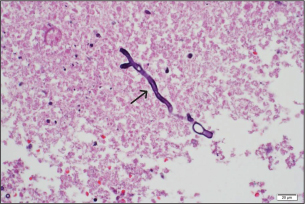

One week after surgery, follow-up brain CT showed enlargement of multiple ring-enhancing lesions in the left frontal, parietal, and occipital lobes, left lateral ventriculitis (Fig. 3). Intraventricular amphotericin B deoxycholate 0.5 mg once daily was added to his antifungal regimen for 14 days due to a lack of radiologic response to ongoing therapy. The fungal isolate was identified as Aspergillus fumigatus on Sabouraud dextrose agar media of abscess and CSF; greenish, powdery, non-velvety colonies and lactophenol cotton blue staining showed septate hyphae, dichotomous branching, columnar conidial head, flask-shaped vesicle, limited phialide upper half of two-thirds of the vesicle, and uniseriate conidia head. Polymerase chain reaction (PCR) analysis of the brain abscess confirmed Aspergillus fumigatus, while bacterial cultures and PCR were negative (Table 2). HIV testing was negative, and lymphocyte subset analysis (CD3, CD4, and CD8) and serum immunoglobulin levels (IgA, IgE, IgG, and IgM) were within normal ranges. Neutrophil oxidative burst testing (NBT) or Dihydrorhodamine test (DHR) and lymphocyte proliferation assays were deferred, as these tests should be performed at least 1 month after blood transfusion to ensure accurate results.

Fig. 3. A computed tomography scan of the brain with contrast on day 23 of admission showed two ring-enhancing lesions located in the left occipital lobe (black arrow) and left periventricular region, adjacent to the lateral ventricle (white arrow).